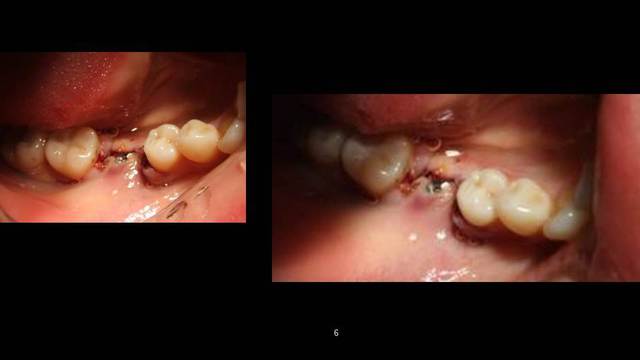

je pense que j'aurais au moins fait la carie en distal de 45 avant de mettre la couronne en 46

Image001 e0kg9q - Eugenol

+1

et 16 et 35; c'est assez énorme!